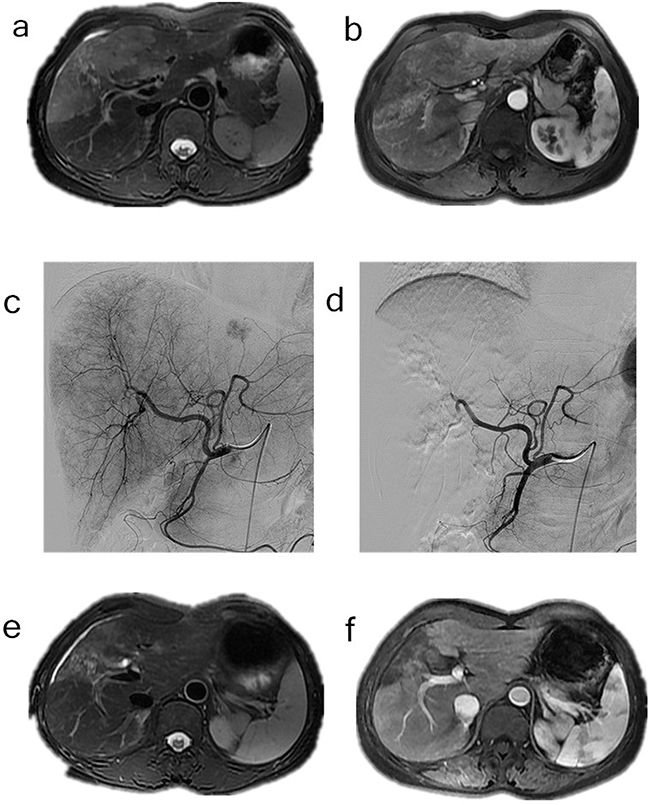

The tumor response was evaluated using CT/MRI according to the mRECIST criteria [7]. Following the HepaSphere microsphere treatment, two patients (6.7%) had complete responses (CR) (Figure 1), 17 (56.7%) had partial responses (PR) (Figure 2), seven (23.3%) had stable disease (SD), and four (13.3%) had progressive disease (PD). The total objective response was 63.3%, and the disease control rate was 86.7%. The pre-TACE and post-TACE tumor indicator details are given in Table 1, and many of the tumor markers had decreased one month postembolization.

Figure 2: a-b. Contrast-enhanced MRI and CT scan done before the procedure in the patient with cholangiocarcinoma, c. Common hepatic artery angiography of the patient with cholangiocarcinoma, d. After chemoembolization angiography with extraction of pathologic vascularization, e-f. Gadolinium contrast MRI control 6 months after TACE, extraction of the vascularization of the tumor.